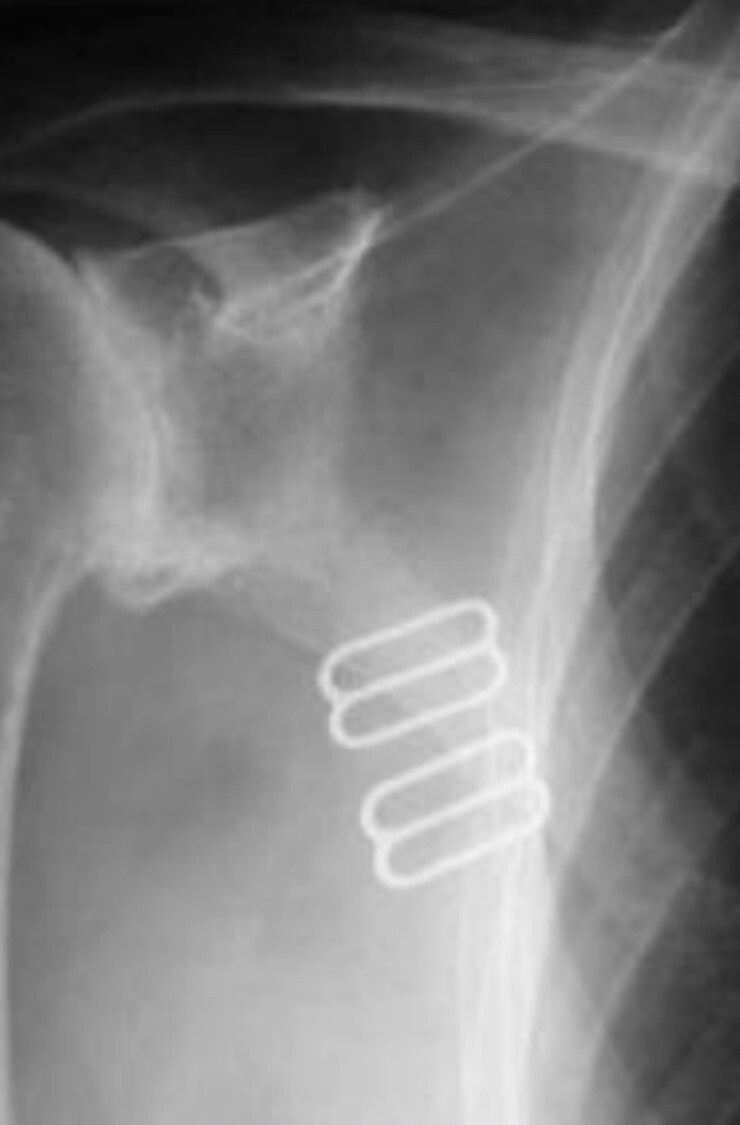

10

Q

What is the cause of the artifact seen in the

attached image?

A

Upside-down focused grid resulting in grid cut-off